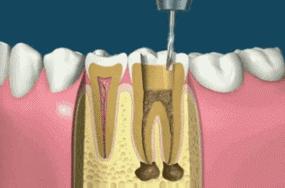

简单来说,根管治疗就是口腔医生把有病变的牙齿打开,然后将牙齿里面发炎、龋坏、坏死的牙髓组织用专业器械清除干净,并把牙髓腔内进行(包含牙髓腔壁)消毒,清洁,最后再用牙胶等物把牙髓腔紧密地封填起来。

在进行根管治疗的时候,拍牙片是必须要的程序的,并且至少要保证3张牙片。

第一张在根管治疗前,拍片可以帮助医生更准确了解牙根的基本情况,以制定治疗计划;

第二张在根管治疗中,可以帮助医生了解治疗的情况,比如根管预备是否到位,方便制定下一步治疗方案;

第三张是在根管治疗结束后,帮助判定根管充填质量,以及治疗效果,发现问题及时补救。